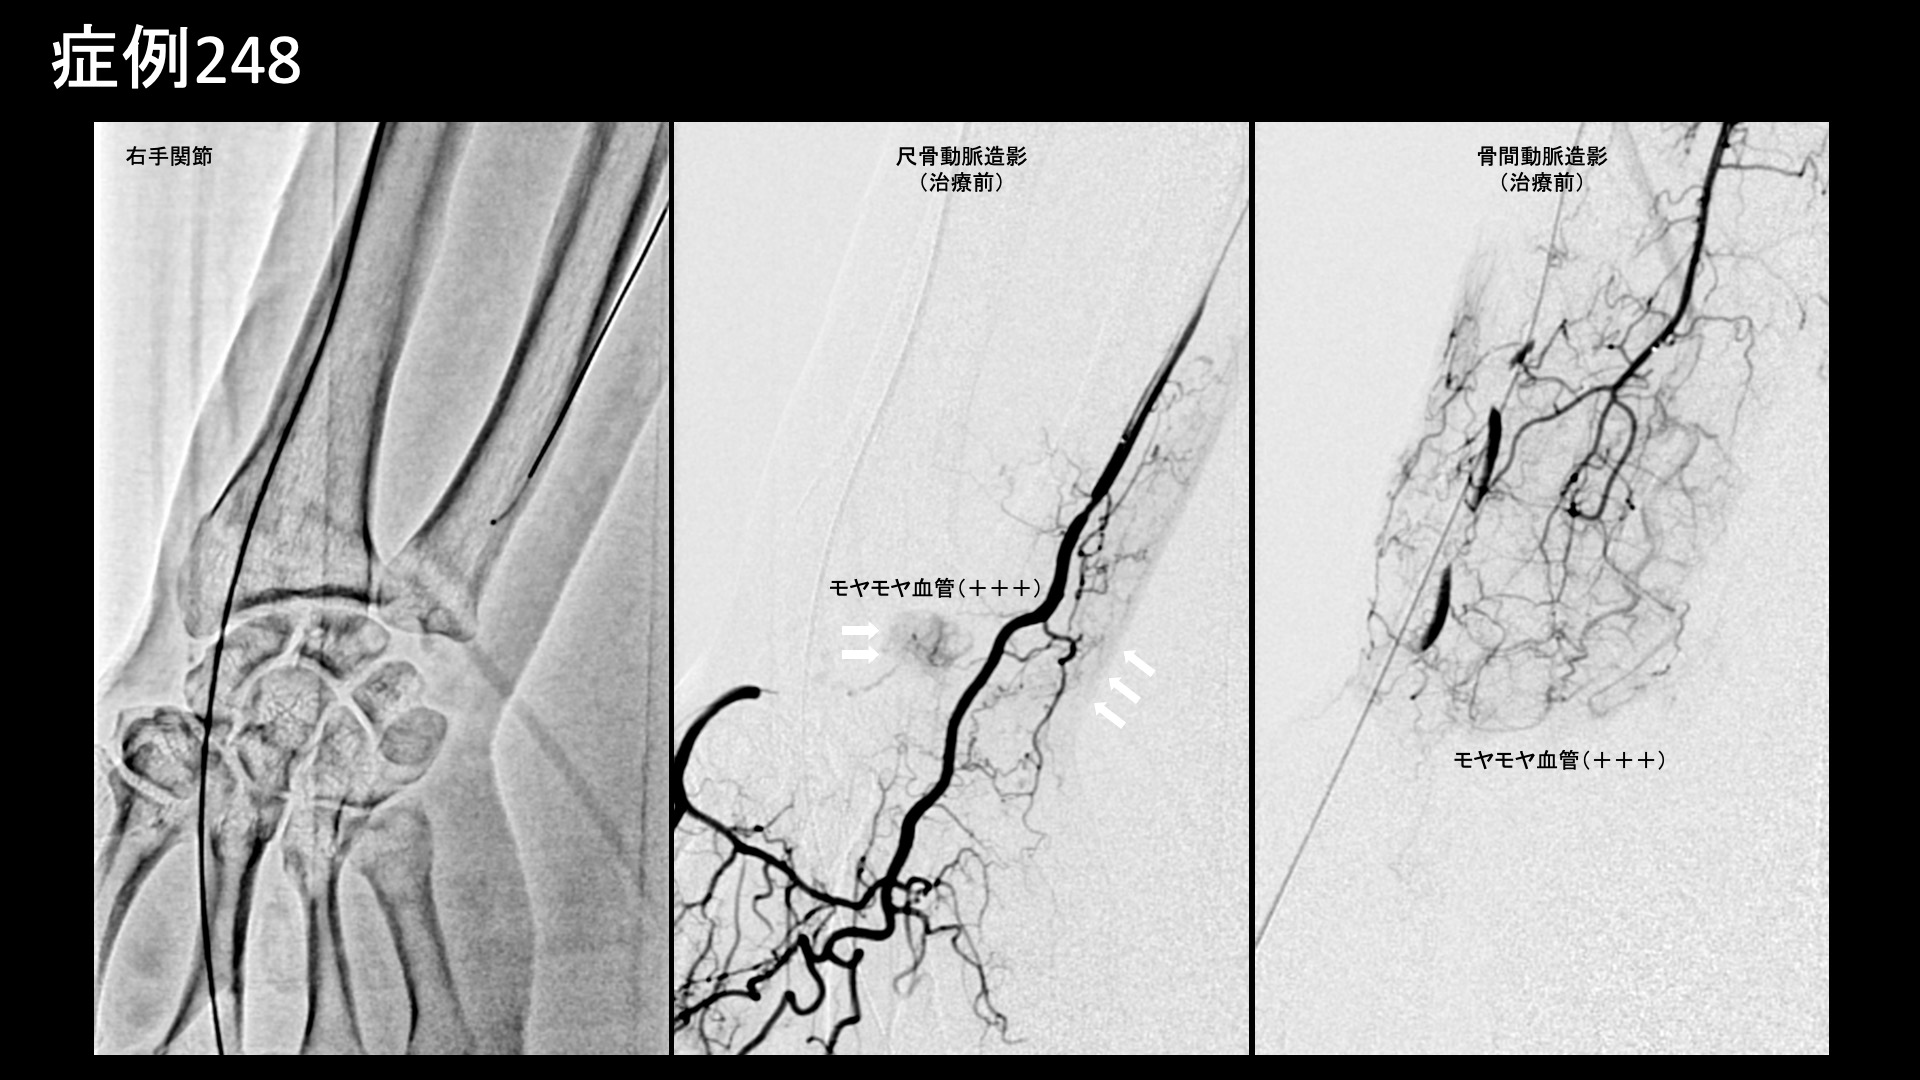

手:ばね指など 【60代:男性】痛くてドアノブも回せない、5年以上続いた手首の痛み。腱鞘炎に変形性手関節症を合併した一例(尺側手根伸筋腱の腱鞘炎、変形性手関節症、ドゥケルバン腱鞘炎) 2025.11.10 鴨井院長による動画解説 受診までの経過 手先をよく使う仕事(巧緻作業)に従事しているほか、趣味で野球やゴルフをされる方です。5年前から右手首が痛むようになりました。使わなければ痛くはならないものの、使うと必ず痛くなりました。ドアノブを回す動作でも痛み、ひどい時は動かせなくなるほどでした。サポーターで固定したりして何とか付き合ってきました。医療機関は度々受診してきましたが、都度レントゲンを撮っても異常は見られず、湿布を処方されるのみでした。この繰り返しで5~6年経過してきましたが、当院の治療を知り受診されました。 診察時の所見 手首の痛みは親指側、小指側とも痛くなるとのことでした。動作確認では、回内回外で特に痛みが誘発されました。背屈はできるものの、一定の可動域制限がありました。エコー検査をすると、尺側手根伸筋腱の腱腫脹および、腱鞘肥厚を認めました。橈側ではより軽度でしたが、一定の腱鞘炎が見られました。更に、手関節橈側において、骨表層不整および低エコー領域を認め、同部位の変形性変化/損傷/変性が示唆されました。レントゲンでは、尺骨に異常は見られなかったものの、手関節の関節裂隙狭小化、および隣接橈骨の骨硬化像を認めました。以上より、尺側手根伸筋腱の腱炎/腱鞘炎、ドゥケルバン腱鞘炎、手関節における変形性関節症と診断しました。治療適応と判断し、モヤモヤ血管(病的新生血管)に対する運動器カテーテル治療(微細動脈塞栓術)を受けていただきました。 治療の所見 血管造影を行うと、尺骨動脈で尺側手根伸筋腱および手関節に一致して、モヤモヤ血管が濃染像として描出されました。骨間動脈でも手関節周囲に、同様にモヤモヤ血管を認めました。治療後は画像上速やかに消失しました。橈骨動脈の治療も行い終了しました。 治療後の経過 治療後2週間ではまだ大きな変化はありませんでしたが、治療後2ヶ月の再診時には大幅に改善し、元の痛みの1/10程度となっていました。しばらく止めていたゴルフもしたいくらいと言われました。その後も再発することなく順調に経過し、治療後6ヶ月時点では、普段の痛みはゼロ、無理をすると痛むことはあるがそれでも当初の1/10とのことでした。腱鞘炎のみではなく、手首の変形性関節症も伴っているため、使い過ぎにはくれぐれも注意していただくようお話しし、終診としています。 腱鞘炎の詳細はこちら 【50代:女性】長い距離を歩くと痛くなる、登山家に生じた両膝の痛みに対するモヤモヤ血管治療(膝蓋下脂肪体炎、腸脛靭帯炎) 前の記事 【50代:女性】ステロイド軟膏塗布が原因で3年以上続いた顔面酒さに対するモヤモヤ血管治療(顔面酒さ、ステロイド性皮膚炎) 次の記事